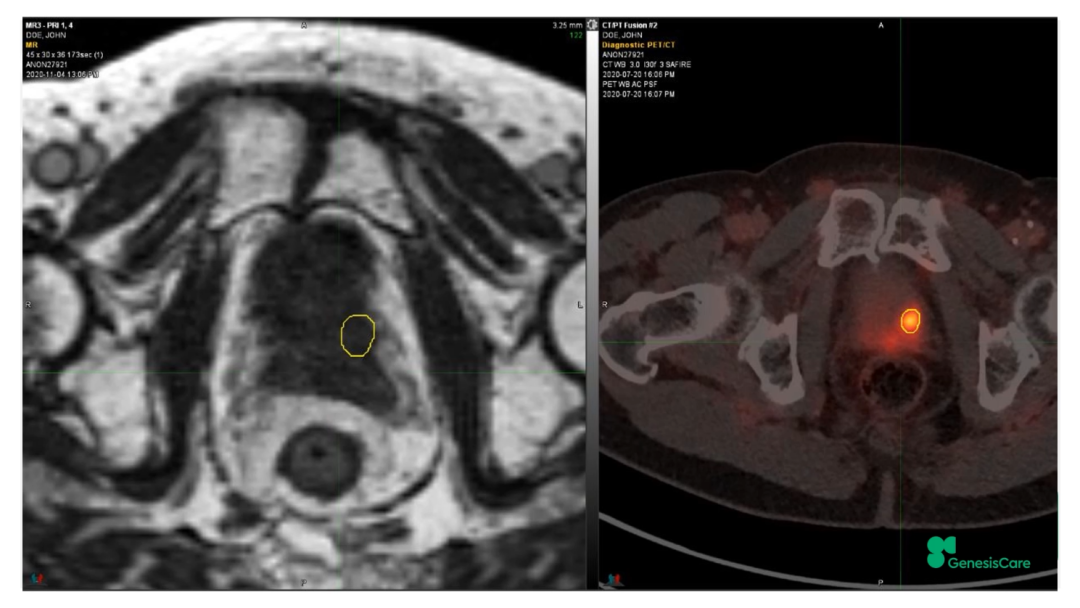

Dr. CamilleriÏÈÈÝÁËһλ72Ë꣬£¬£¬£¬£¬£¬ÔÚ2006Äê½ÓÊÜÁË55Gy/20F·ÅÁƺ󸴷¢µÄǰÏßÏÙ°©»¼Õß¡£¡£¡£¡£¡£¡£¡£ÆäʱËüµÄPSAΪ28£¬£¬£¬£¬£¬£¬¾Ö²¿ÍíÆÚ£¬£¬£¬£¬£¬£¬ÆÚ±ðΪT3aN0M0¡£¡£¡£¡£¡£¡£¡£PET-CTÏÔʾǰÏßÏÙ×óºó²¿¾Ö²¿¸ß´úл£¬£¬£¬£¬£¬£¬»î¼ìҲ֤ʵÁËÕâÒ»µã£¬£¬£¬£¬£¬£¬²¢ÇÒ»î¼ìЧ¹ûÅú×¢Ö×ÁöÇÖÈë×ó²à¾«ÄÒÏٵײ¿¡£¡£¡£¡£¡£¡£¡£½«ÆäMRIdian MRIͼÏñºÍPET-CTͼÏñÈںϺ󣬣¬£¬£¬£¬£¬ÔÙÆ¾Ö¤»î¼ìЧ¹ûÈ·¶¨°ÐÇø£¬£¬£¬£¬£¬£¬¼ûFigure 20-22£¬£¬£¬£¬£¬£¬²¢ÖÆ×÷·ÅÁÆÍýÏë¡£¡£¡£¡£¡£¡£¡£·ÅÁƼÁÁ¿Îª35Gy/5´Î£¬£¬£¬£¬£¬£¬Äý½º×è¸ôÎïºÜºÃµØ°üÀ¨ÁËÖ±³¦£¬£¬£¬£¬£¬£¬¼ûFigure 23£¬£¬£¬£¬£¬£¬°ÐÇøºÍΣ¼°Æ÷¹ÙÊÜÁ¿¼ûFigure 24¡£¡£¡£¡£¡£¡£¡£»£»£»£»£»£»£»£»¼ÕßÓÚ2020Äê12Ô½ÓÊÜÖÎÁÆ£¬£¬£¬£¬£¬£¬ËûÌåÖʺܺ㬣¬£¬£¬£¬£¬ÔÚ·ÅÁÆÊ±´úºÍÖ®ºó£¬£¬£¬£¬£¬£¬¼á³ÖÿÖÜÈý´Î5¹«ÀïÅܲ½£¬£¬£¬£¬£¬£¬Ê¼ÖÕδ·ºÆðGUºÍGI¶¾ÐÔ¡£¡£¡£¡£¡£¡£¡£ËûµÄPSA×îµÍֵΪ0.45£¬£¬£¬£¬£¬£¬ÔÚ2022Äê5ÔµÄËæ·ÃÊý¾ÝÖУ¬£¬£¬£¬£¬£¬ØºÍè¼¤ËØË®Æ½»Øµ½ÁËÕý³£µÄ33%¡£¡£¡£¡£¡£¡£¡£ÔÚ2022Äê1ÔµķÅÁƺóPSMA PETµÄͼÏñÉÏ£¬£¬£¬£¬£¬£¬Î´¼ûÖ×Áö¸ß´úл¼ûFigure 25¡£¡£¡£¡£¡£¡£¡£